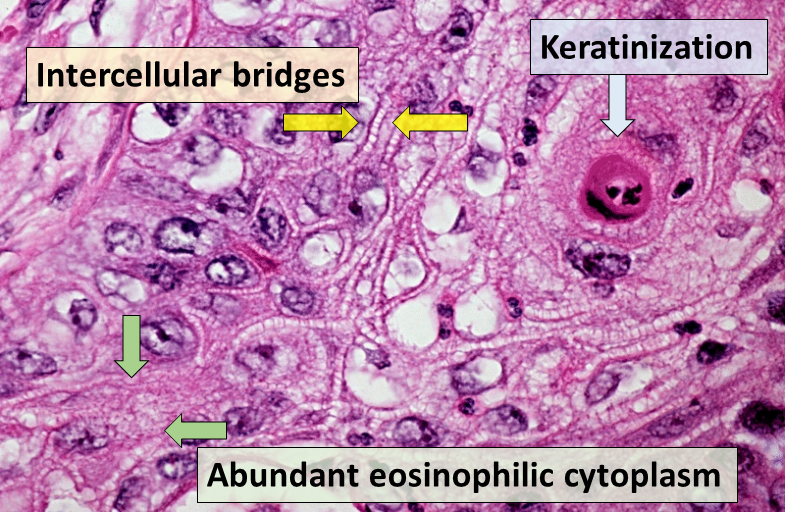

Squamous Cell Carcinoma

Squamous cell carcinoma (SCC) is the second most frequently diagnosed cancer worldwide.

Squamous cell carcinoma (SCC) accounts for about 30% of cancer cases in men and 20% of cases in women.

Two important risk factors for squamous cell carcinoma (SCC) are alcohol and tobacco use.

Invasive squamous cell carcinoma (SCC) may develop from oral leukoplakias and erythroplakias, which are precancerous diseases.

Although they can appear anywhere in the oral cavity epithelium, these lesions typically grow at the mouth’s floor.

Histologically, squamous cell carcinoma (SCC) is identified by alterations in the stratified squamous epithelial layers, such as invasion into the underlying connective tissue and hyperkeratosis, parakeratosis, acanthosis, keratin pearls, and dysplasia.